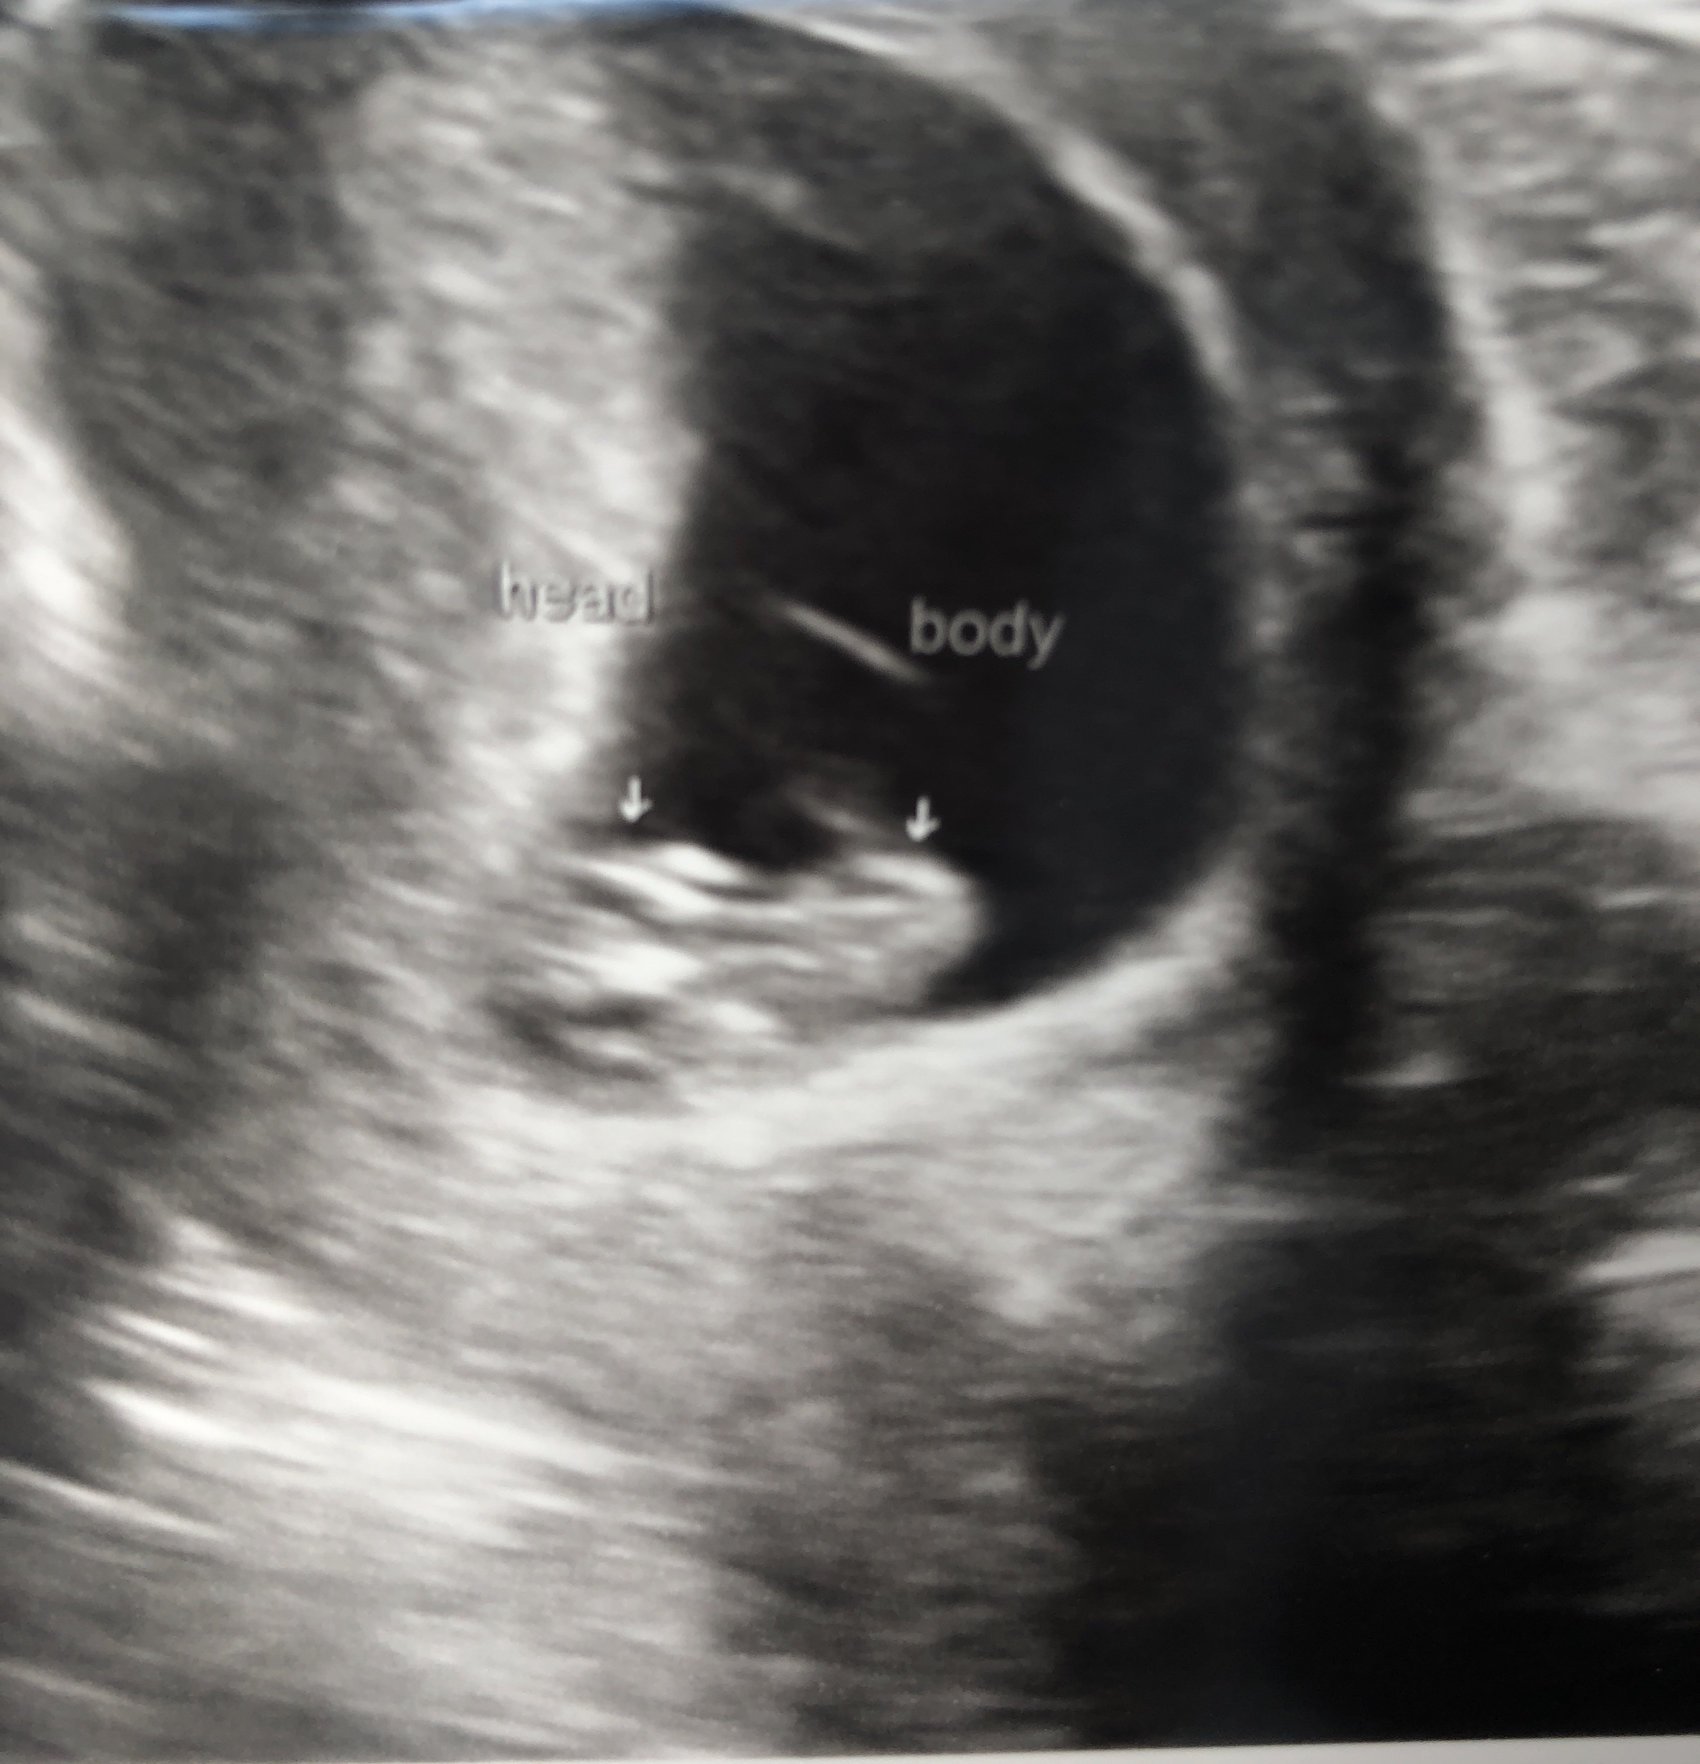

7w0d heartbeat 120

6w1d HB: 111 ♥️ little blob